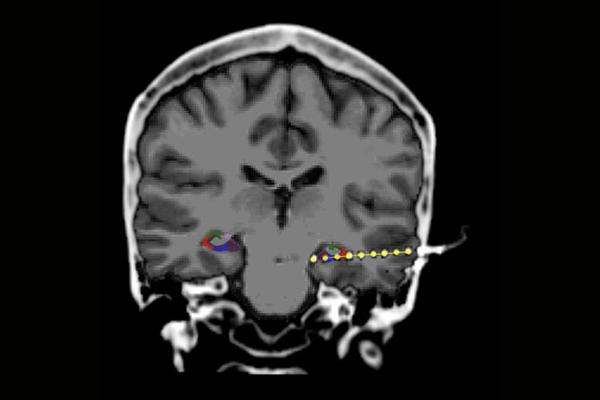

image: Electrode (yellow dots) implanted in the hippocampus of a patient undergoing epilepsy monitoring, viewed with MRI. Colors indicate sub regions of the hippocampus. Sharp wave ripples appear most prominently in the CA1 region, shown in red.

Humans can, of course, communicate their thoughts, but most research methods do not give scientists a detailed view of what happens at the same time within the brain. Yitzhak Norman, a PhD student in Malach's lab, who led the current research in collaboration with the group of Prof. Ashesh Mehta from the Feinstein Institute for Medical Research in the US, recruiting patients who undergo invasive recordings in the course of their medical diagnosis. In this clinical procedure, patients suffering from intractable epilepsy get electrodes implanted in multiple brain regions to locate the epileptic focus and surgically remove it. These patients freely volunteered to participate in the memory experiments while they waited in the hospital between seizures.